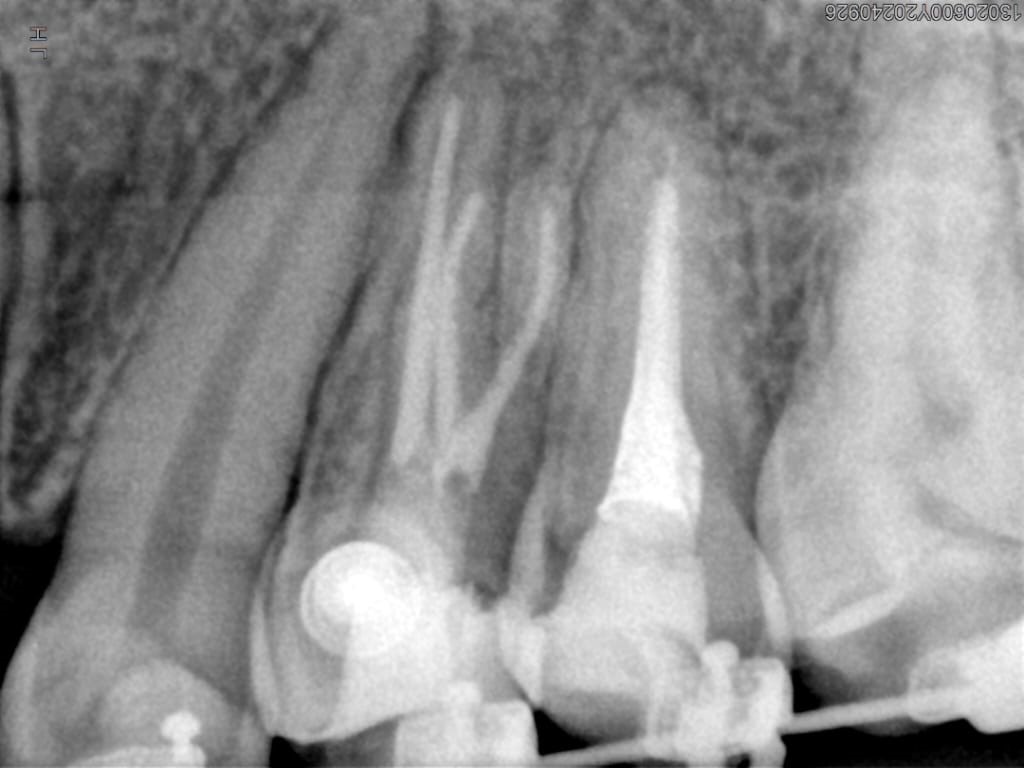

Veja alguns casos de sucesso